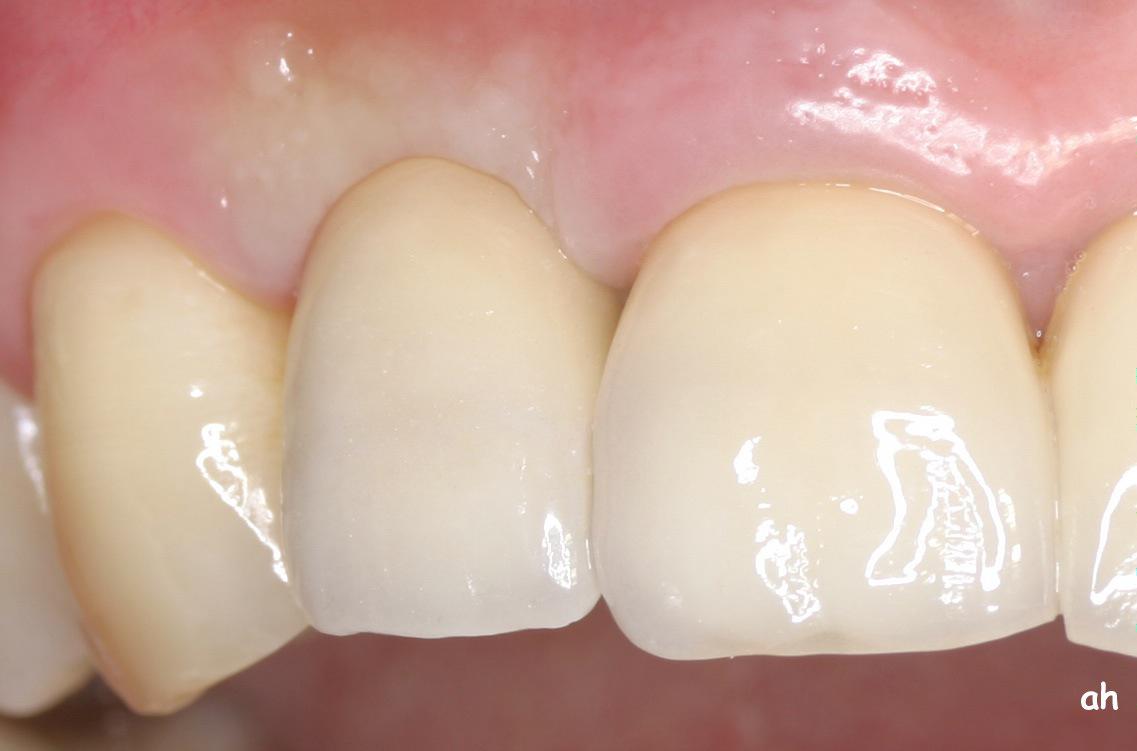

Exemple 1: résultat final.

Exemple 11: La couronne céramique en place.